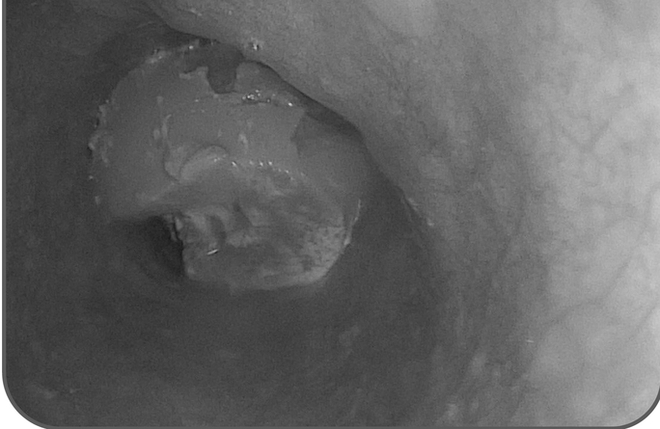

Đến khoảng 17 giờ cùng ngày, tình trạng vẫn không thuyên giảm nên ông được người nhà đưa đến Khoa Cấp Cứu - Bệnh viện Đa khoa Xuyên Á Long An. Các bác sĩ đã nội soi và phát hiện khối thức ăn dai với kích thước khoảng 6 cm kẹt 1/3 giữa thực quản. Sau đó, các bác sĩ tiến hành dùng đầu ống soi đẩy khối thức ăn xuống dạ dày, kiểm tra không ghi nhận trầy xước. Bệnh nhân đã ổn định sức khoẻ sau khi được can thiệp.

Cục gân bò có kích thước lớn kẹt tại thực quản của người đàn ông (Ảnh: BVCC)